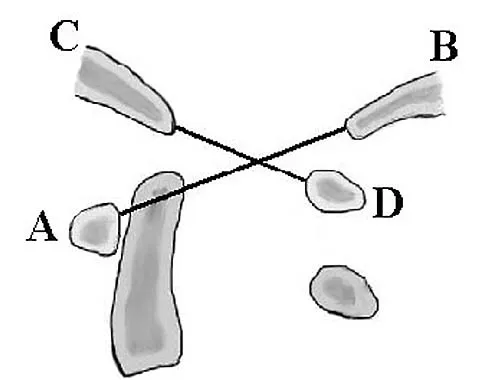

In a postganglionic brachial plexus lesion at Erb's point (point of formation of the upper trunk by the C5 and C6 nerve roots), which of the following nerves will still function normally?